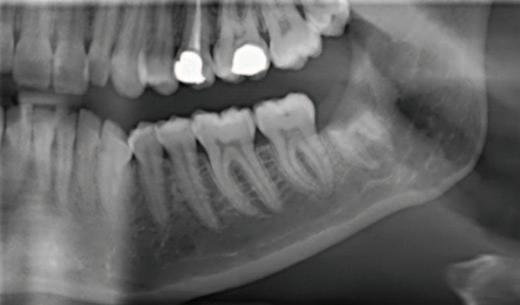

At the oral surgery consultation, the patient also noted a four-week history of intermittent discomfort in the LL8 region, described as throbbing pain with associated swelling of the gum, made worse by chewing and applying pressure to the tooth. This presentation was in keeping with recurrent pericoronitis. A cone-beam computed tomography (CBCT) scan was undertaken, which identified four roots of LL8 and associated loss of IAN canal cortication. The IAN pathway grooved the distobuccal root and passed between/penetrated the mesial roots (Figures 2 and 3).

FIGURE 2: Association of IAN with mesial roots (L = lingual, B = buccal, IAN = inferior alveolar nerve).

FIGURE 3: Association of IAN with distal roots (L = lingual, B = buccal, IAN = inferior alveolar nerve).